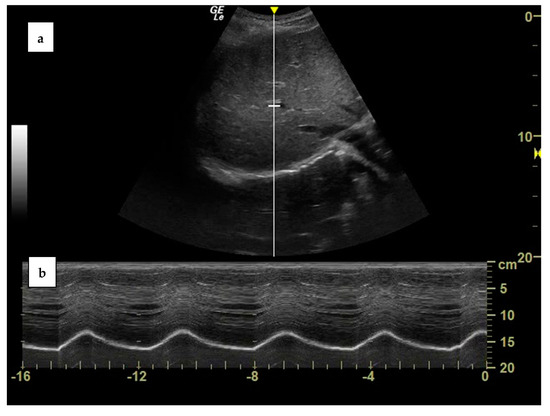

3.1. Clinical Case One